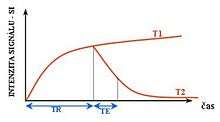

Contrast

Image contrast may be weighted to demonstrate different anatomical structures or pathologies. Each tissue returns to its equilibrium state after excitation by the independent processes of T1 (spin-lattice) and T2 (spin-spin) relaxation.

To create a T1-weighted image, magnetization is allowed to recover before measuring the MR signal by changing the repetition time (TR). This image weighting is useful for assessing the cerebral cortex, identifying fatty tissue, characterizing focal liver lesions and in general for obtaining morphological information, as well as for post-contrast imaging.

To create a T2-weighted image, magnetization is allowed to decay before measuring the MR signal by changing the echo time (TE). This image weighting is useful for detecting edema and inflammation, revealing white matter lesions and assessing zonal anatomy in the prostate and uterus.